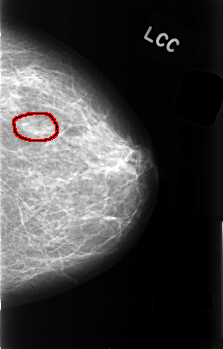

C_0489_1.LEFT_CC

LEFT_CC LINES 4528 PIXELS_PER_LINE 2896 BITS_PER_PIXEL 12 RESOLUTION 50 OVERLAY

FILE: C_0489_1.LEFT_CC.OVERLAY

TOTAL_ABNORMALITIES 1

ABNORMALITY 1

LESION_TYPE MASS SHAPE OVAL MARGINS ILL_DEFINED

ASSESSMENT 3

SUBTLETY 4

PATHOLOGY BENIGN

TOTAL_OUTLINES 1

BOUNDARY